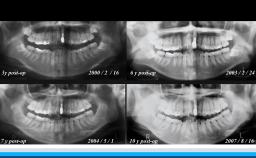

高齢者の咬合力回復は,栄養摂取や全身の筋力維持に貢献できる.インプラント治療もQOL向上に大きく寄与できる可能性を有する.一方,術後の全身の健康状態の変化に対応したメンテナンスを術前から考える必要がある.

• Long-Term Data

• Outcomes